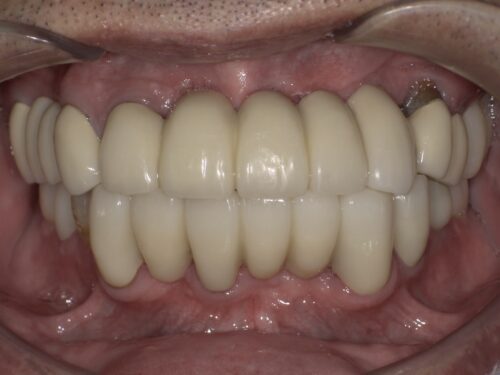

治療後の写真です。

前歯はブリッジとよばれる治療法で治しました。

根元の歯ぐきは赤みがなくなり健全な状態になりました。

奥歯でもしっかり噛めるようにすることで前歯にかかる負担を軽減しています。

前歯の傾きも改善して、上下の前歯が本来の位置関係で噛めています。

ただ、歯周病の影響で歯ぐきが下がっており、そこのブラッシングはしっかり続けていく必要があります。

歯一本一本だとグラグラしてしまうような状態でも、

ブリッジといってかぶせ物でつなぐことで全体として強度が上がるようにしています。

下の奥歯はインプラントを入れることで噛める範囲を増やしています。